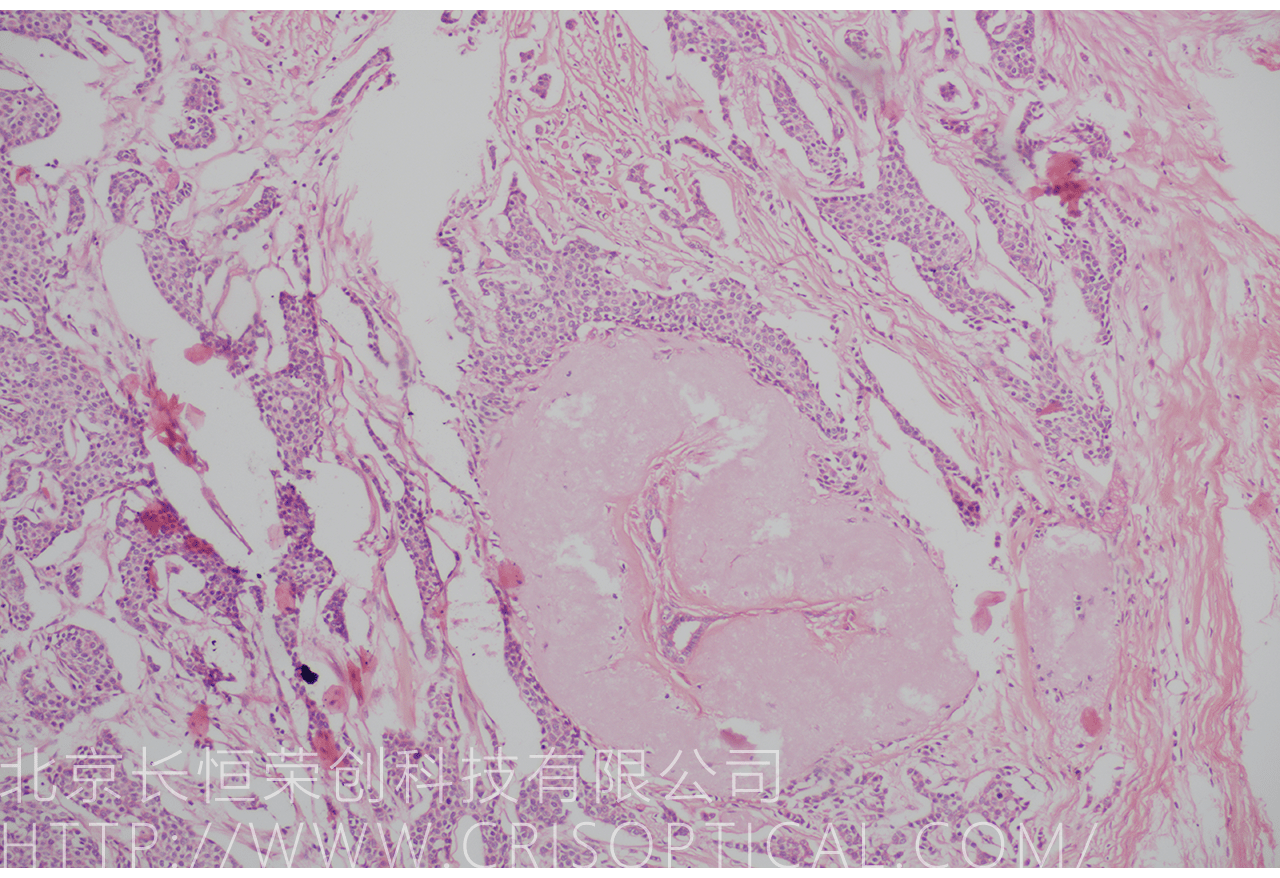

腫瘤診斷:對(duì)癌癥和其他腫瘤的病理切片觀察是確定腫瘤類型、分級(jí)和分期的關(guān)鍵步驟。醫(yī)生通過觀察組織樣本中的細(xì)胞形態(tài)、核形狀、分裂活性和其他特征,可以識(shí)別腫瘤的類型,幫助決定治療方法。

外科手術(shù)指導(dǎo):在外科手術(shù)中,醫(yī)生可能會(huì)采集組織標(biāo)本,然后由病理學(xué)家進(jìn)行切片制備和觀察。手術(shù)中的快速冰凍切片術(shù)可以提供實(shí)時(shí)的病理診斷,幫助外科醫(yī)生確定手術(shù)范圍、移除腫瘤或其他異常組織。